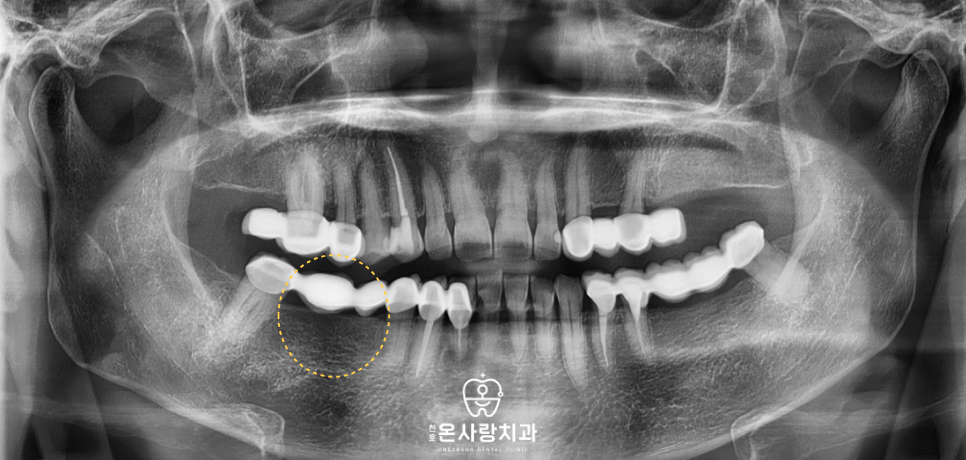

또한 기존에 치아가 비어 있던 자리에는

인공치아인 천호역임플란트를 식립함으로써

브릿지에만 의존하던 구조에서 벗어나

각 치아가 독립적으로 씹는 힘을

견딜 수 있도록 재구성하였습니다.